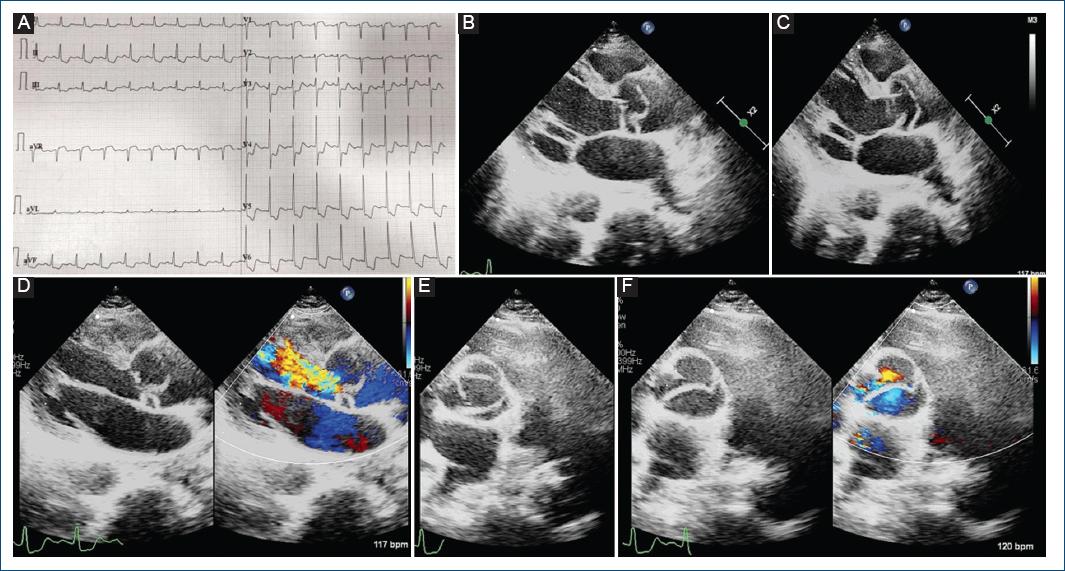

A middle-aged woman with no comorbidities presented to the emergency department with chest discomfort and breathlessness. Vitals showed tachycardia, hypotension, and a soft early diastolic murmur, and a chest X-ray revealed acute pulmonary edema. Twelve lead electrocardiogram (Fig. 1A) showed sinus rhythm with ST depression in 2, 3, aVF, V3-V6, ST elevation in aVR, and lead 1 suggestive of an acute coronary syndrome involving the left main coronary artery. A transthoracic echocardiogram showed severe left ventricular dysfunction, global LV hypokinesia, and a tricuspid aortic valve with an oscillating flap-like structure was observed in the ascending aorta; indicating an acute aortic dissection (Fig. 1B-F). The patient was shifted for emergency surgery after computed tomography-Aortography, which confirmed the diagnosis of De-Bakey Type I dissection with a curvilinear dissection flap extending from the ascending aorta, involving the arch of aorta up to the right common femoral artery (Fig. 2D and E). The dissection flap is seen occluding the Left main with hypoperfusion in the left anterior descending and left circumflex (Fig. 2A and B), with the right coronary artery being spared (Fig. 2C). Despite the surgery, the patient did not survive in the post-operative period.

Figure 1 A: 12 lead electrocardiogram suggestive of left main coronary artery occlusion with global ST depression and aVR ST elevation. B-D: 2D transthoracic echocardiogram images in parasternal long axis view showing curvilinear dissection flap in the ascending aorta causing severe aortic regurgitation. E and F: 2D transthoracic echocardiogram images in parasternal short axis view showing trileaflet aortic valve and aortic dissection flap impeding the mobility of aortic valve leaflets.